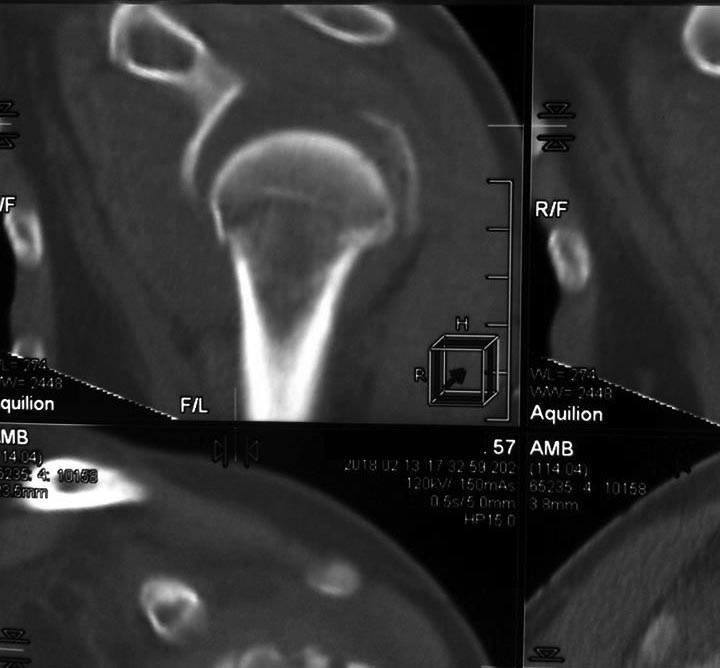

[Ortho] Перелом проксимального метаэпифиза плеча

Дорогие коллеги! Мнение о тактике лечения пациентки в нашем отделении

разделилось.

травма 10 дней назад, падение при катании на обычных лыжах. Сама

врач-рентгенолог 57 лет.

Левая рука, недоминатная. На данный момент ходит в косынке, вся в

сомнениях, что делать.

Мнения по лечению: - ничего не делать - остеосинтез пластиной

блокированной - первичное эндопротезирование (в наличие только геми,

delta не потянет) Может кто-то что более дельное предложит.